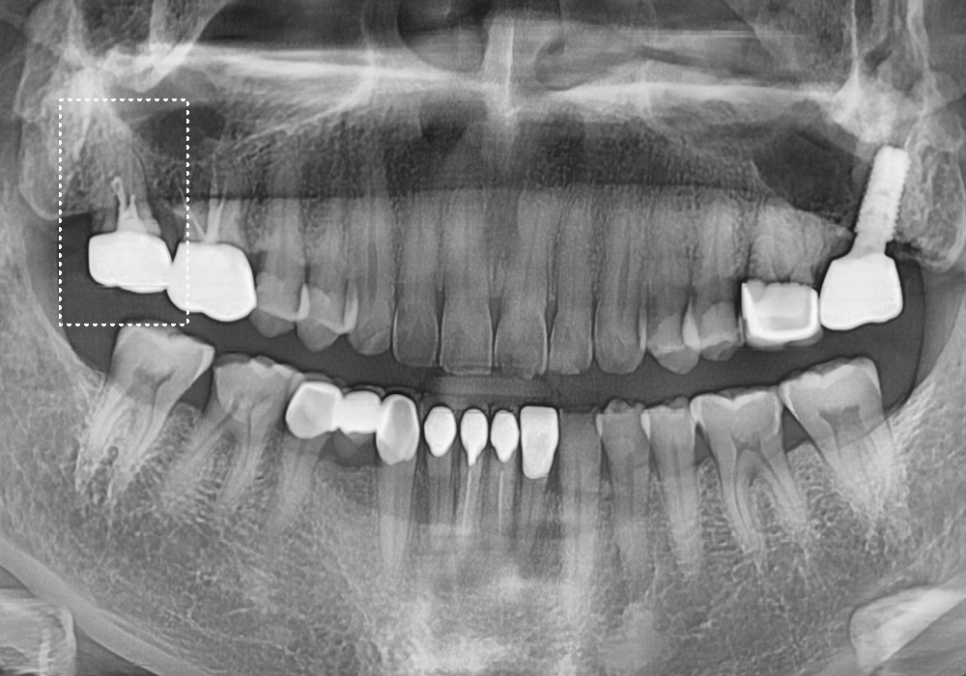

치료 결과

치료를 마친 지 2주 뒤,

경과를 확인하기 위해 내원하셨는데요.

240325

다행히 아픈 느낌 없이

편하게 식사하고 계신다고 하네요~

자칫하면 발치까지 고민하셨던 터라

그 만족감이 더 크셨던 것 같아요.^^